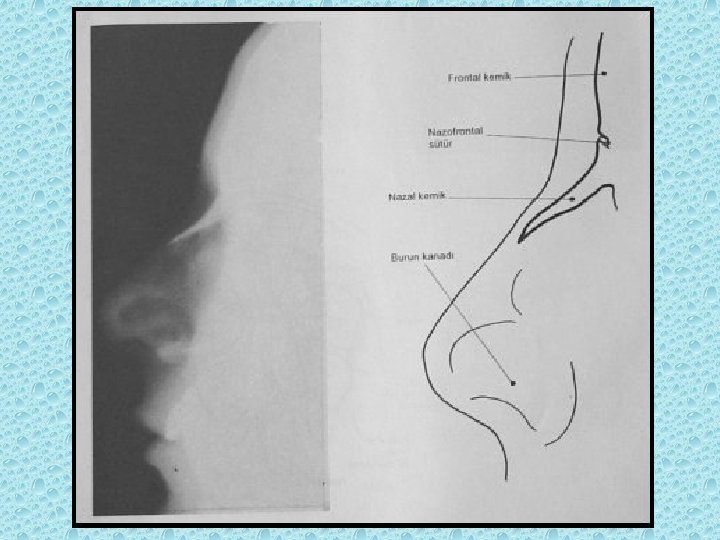

NAZAL BOŞLUKTAKİ YAPILAR • • Konkalar: alt, orta, üst Meatüsler: Alt, orta, üst Nazal septum Koana

YÜZ KEMİKLERİ • • Maksiller Etmoid Frontal Mandibula Nazion Zigoma Lakrimal Palatin